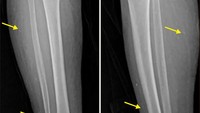

Benang-benang emas yang dimasukkan dalam tubuh dapat bermigrasi di dalam tubuh dan merusak jaringan sekitarnya. Misalnya pada kasus pasien berusia 75 tahun di Korea Selatan, benang emas yang ditanamnya di punggung bermigrasi ke area kaki bagian kanan dalam waktu kurang dari 10 tahun. (Foto: Annals of Dermatology)